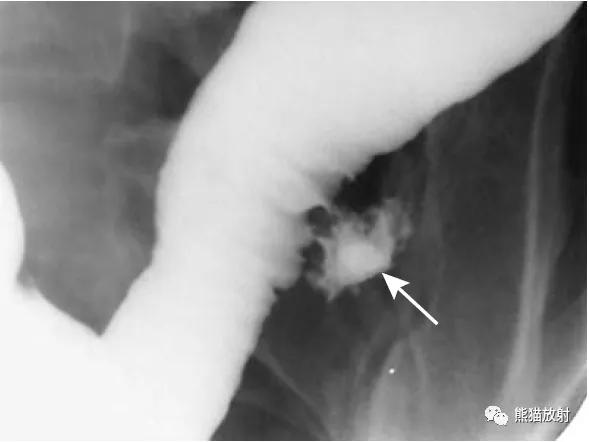

结-结肠肠套叠,由盲肠癌所致。钡灌肠显示横结肠中的肠套叠(箭头),在进一步的压力下,肠套叠移位至升结肠。